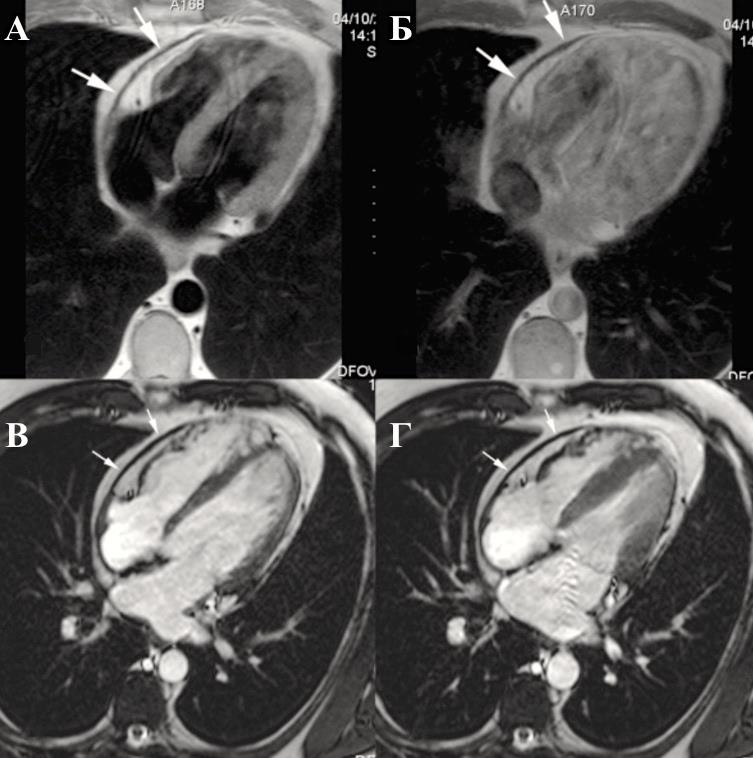

Констриктивный перикардит характеризуется утолщением перикарда, которое больше выражено со стороны правого желудочка и передней атривентрикулярной борозды (Приложение А3, рис. 12) [156].

При этом критериями утолщения листков на МРТ считаются [157]:

Утолщенный перикард имеет слабую интенсивность сигнала не только на Т1- и Т2-взвешенной спин-эхо МРТ, но и на кино-изображениях; в терминальной стадии констриктивного перикардита введения парамагнитных контрастных средств (гадолиний-содержащих) не приводит к увеличению детализации изображения (Приложение А3, рис. 13) [158].

Косвенными признаками констриктивного перикардита будут: расширение предсердий, дилатация полых и печеночных вен, асцит и плеврит.

В случаях констриктивного перикардита выявляются значительное утолщение перикарда, между листками которого обнаруживаются спайки c очагами казеозного перерождения и превращения в рубцовую ткань. Также возможно обнаружение обызвествления околосердечной сумки.